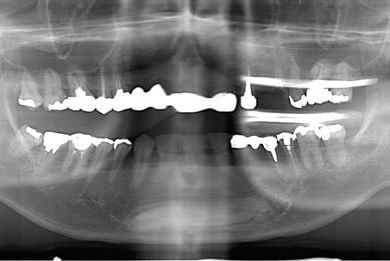

| 性別/年齢 | 男性 / 46歳 | ||||||||||||||||||||||||||||||||

| 治療内容 | インプラント2本(抜歯即日スピードインプラント)、ハイブリッドセラミック2本 | ||||||||||||||||||||||||||||||||

| 総治療費 | 456,750円 | ||||||||||||||||||||||||||||||||

| 治療期間 | 7ヶ月 |